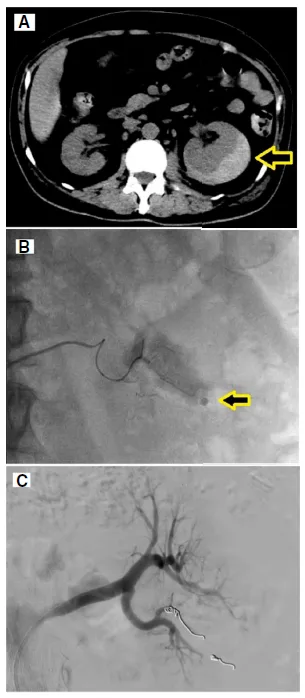

2️⃣ **Tomografia sem contraste**

Confirmou hematoma subcapsular perirrenal esquerdo (3 cm).

4️⃣ **Angiografia renal**

Mostrou extravasamento de contraste de ramo segmentar da artéria renal, confirmando sangramento ativo.

Foi realizada embolização superseletiva da artéria renal com coils, com controle do sangramento.